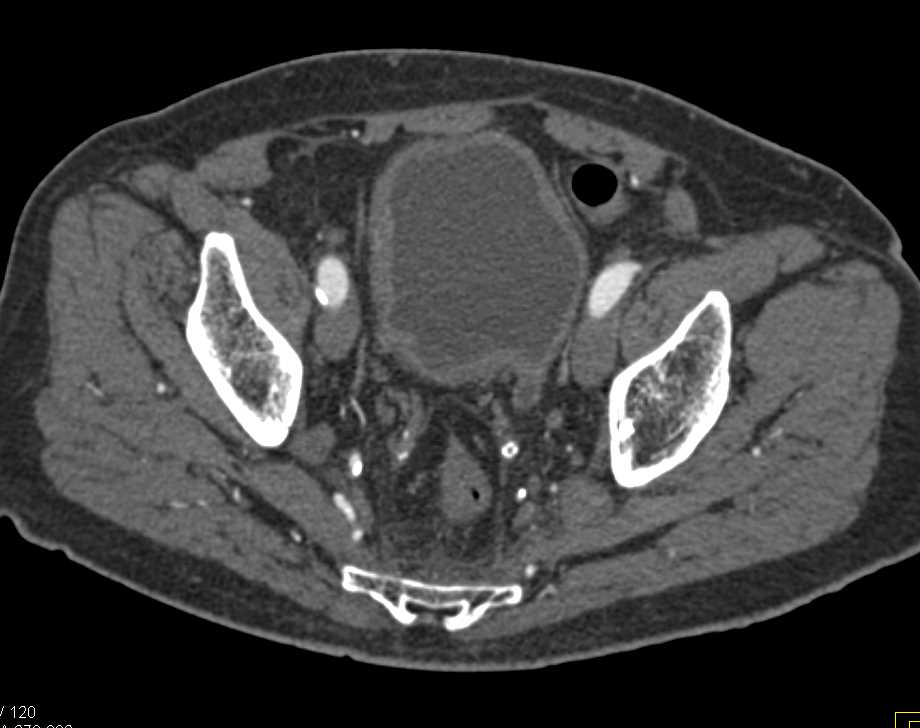

Type B Aortic Dissection